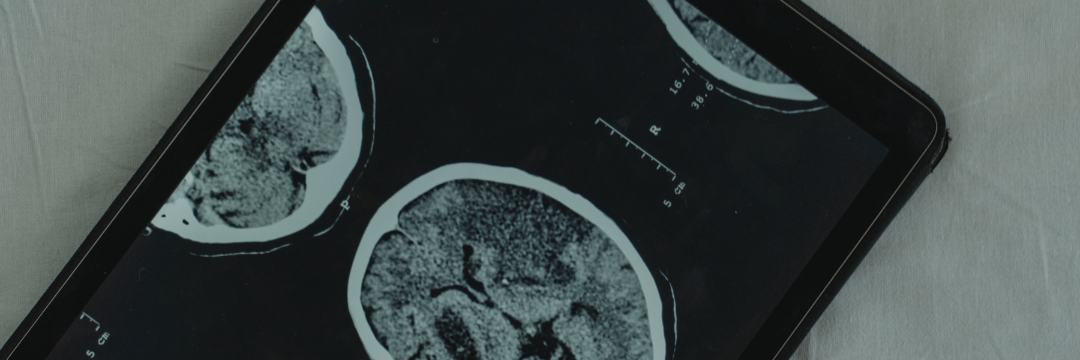

- Decide if imaging (CT/MRI) is needed

- Advanced imaging (CT, MRI, EEG, NCV)